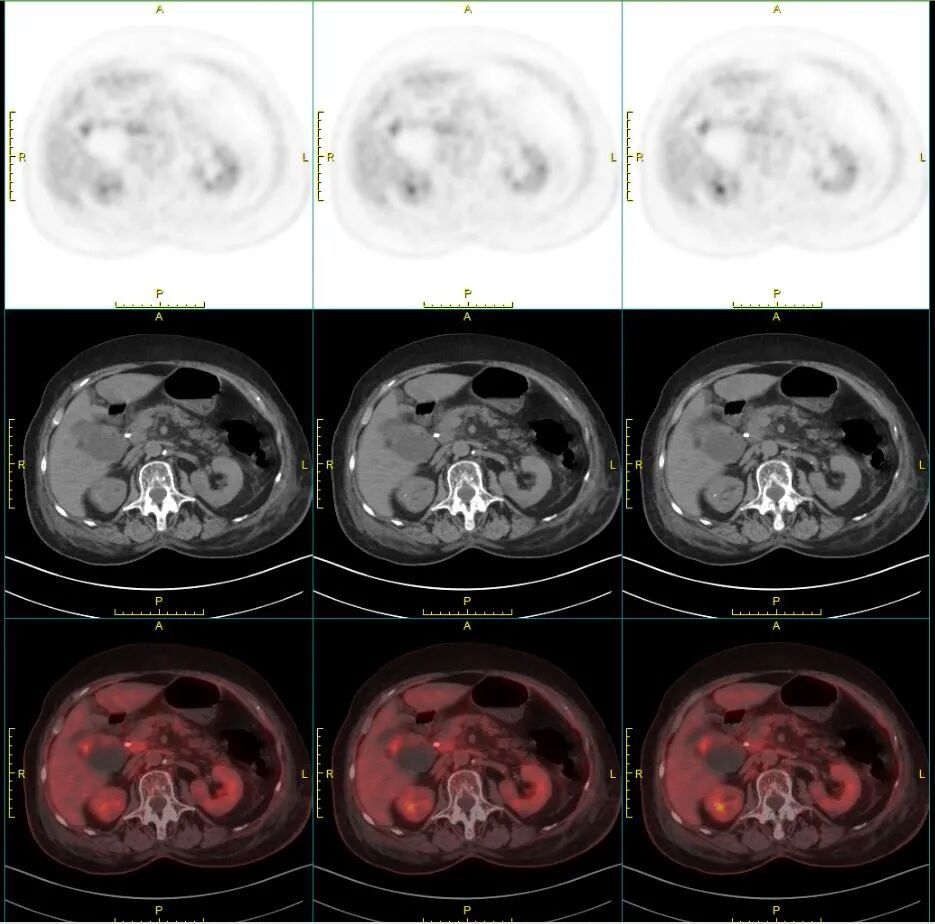

手术后第二天,胆红素就如同预计的那样出现明显下降,淀粉酶也没有明显升高。PET-CT 结果显示除了病灶、局部淋巴结和大网膜的转移外没有发现其他的远处转移灶。好消息!